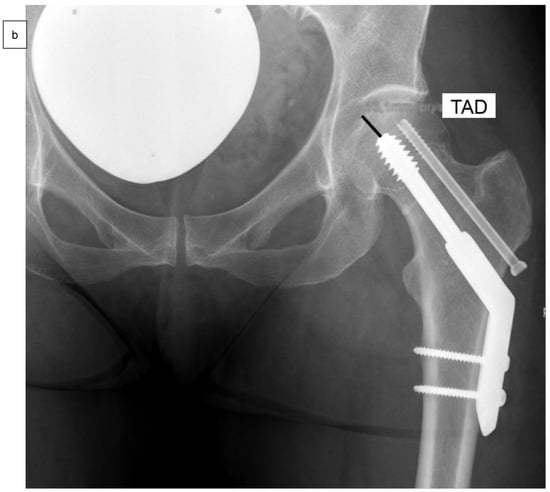

As well as epidemiological patient parameters and the Kellgren–Lawrence score at the time of hospital admission, the femoral neck angles (°) were captured in comparison to the opposite side (Figure 2a) after reduction and surgical stabilization six weeks postoperatively by using biplanar conventional radiographs. Valgus reduction was defined as a femoral neck angle of more than 5° in comparison to the opposite side. Then, the cohort group was divided into group “A”, which included patients with anatomical reduction, and group “B”, which consisted of patients with valgus reduction of the Garden type III femoral neck fracture. Further on, the angle of the 2- or 4-hole SHS plate (°), the tip-apex distance (mm) as described by Baumgaertner et al. (Figure 2b), and the angle between SHS and ARS (°) were measured in frontal (Figure 2c) and axial planes (Figure 2d) of the intraoperative or postoperative X-rays [].

Figure 2.

Measurement of the femoral neck angle (*) compared to the contralateral side (°), defined as the angle between the femoral neck axis and the bisecting line of the femoral shaft (a). The tip-apex distance (TAD) was defined as the calibrated summation of the distance between the tip of the SHS and the apex of the femoral head on anteroposterior and (not demonstrated) lateral radiographs (mm) (b), and the angle between SHS and ASR in the frontal plane (#) (c) and the axial plane (x) (d) by using biplanar conventional radiographs, six weeks postoperatively.